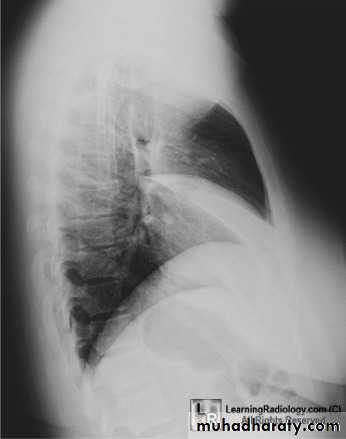

32.RT ML consolidation ( PA & lat. view )

33.RT ML consolidation (Lat. view )